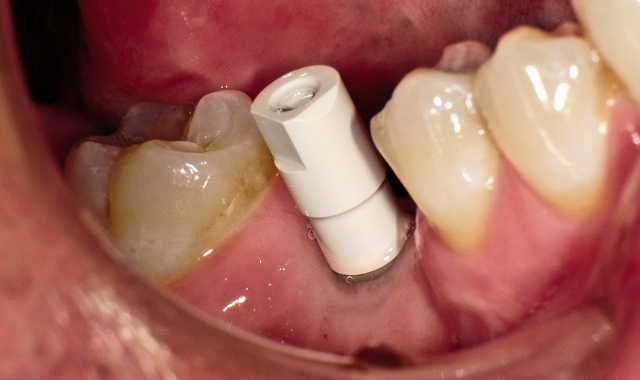

Fig. 1 An intraoral photo shows a patient missing a lower-right first molar

During my initial appointment with a patient, I will capture an image with an intraoral camera (Fig. 1).

Approximately 80 percent of implant cases involve single teeth (Fig. 4).